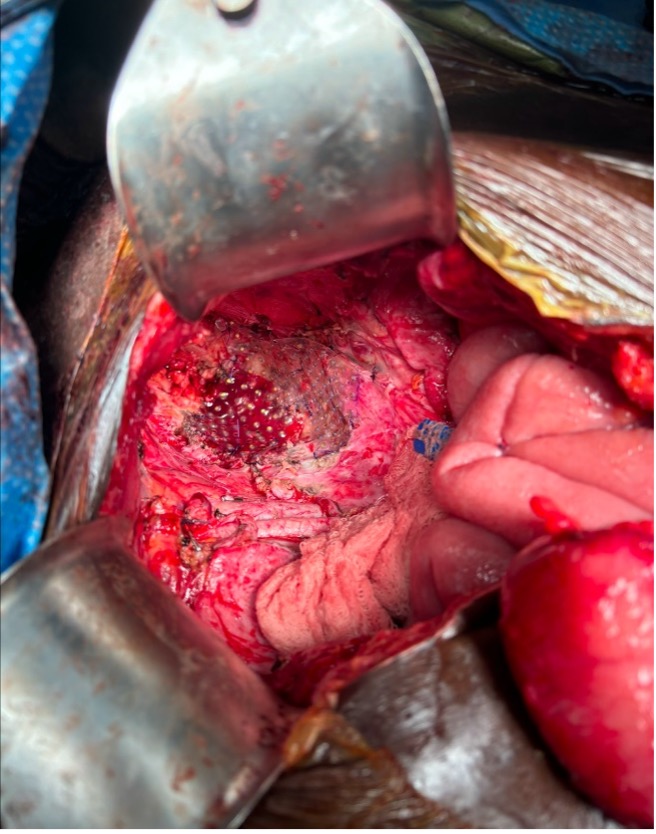

Figure 1. CivaSheet placement and fixation within the pelvis following pelvic exenteration

Figure 1. CivaSheet placement and fixation within the pelvis following pelvic exenteration

Figure 1. CivaSheet placement and fixation within the pelvis following pelvic exenterationTable 1. Patient and cancer characteristics of those who underwent CivaSheet placement 2017-2025.